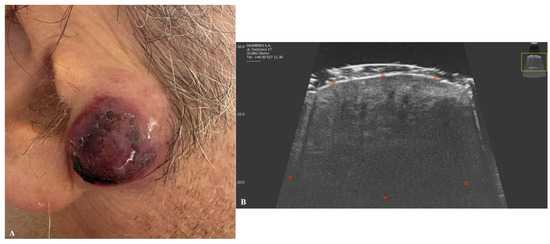

4. Merkel Cell Carcinoma

| Merkel Cell Carcinoma | Hypoechogenic dermal or hypodermal lesion with chaotic vascular patterns. May exhibit hypoechoic linear bands (“plume-of-smoke” appearance). |